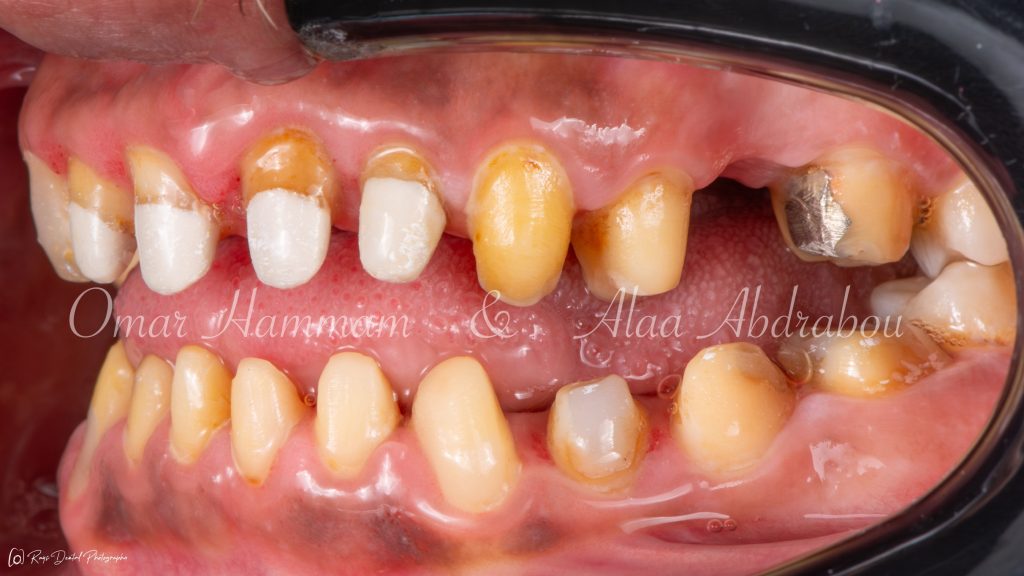

The optimum occlusion tried to be established at the right side to be half unit "Cusp to Cusp" occlusion, as the patient suffers from two different occlusion classes on the both sides and on the same side between the molar and canine relationships, to distribute forces more evenly across the occlusal surfaces promoting stability and longevity of the restoration.

Immediate occlusal scheme after cementation (before any adjustments):

Showing “Occlusal equilibration”, where Stable occlusion is achieved , in which there are Stable contacts of equal intensities on all teeth in centric occlusion showing Group Function occlusion.

Occlusal forces are distributed on more occlusal contacts, Acting as a group to distribute occlusal forces, thereby increasing efficiency of mastication and performing lateral movements atraumatically.